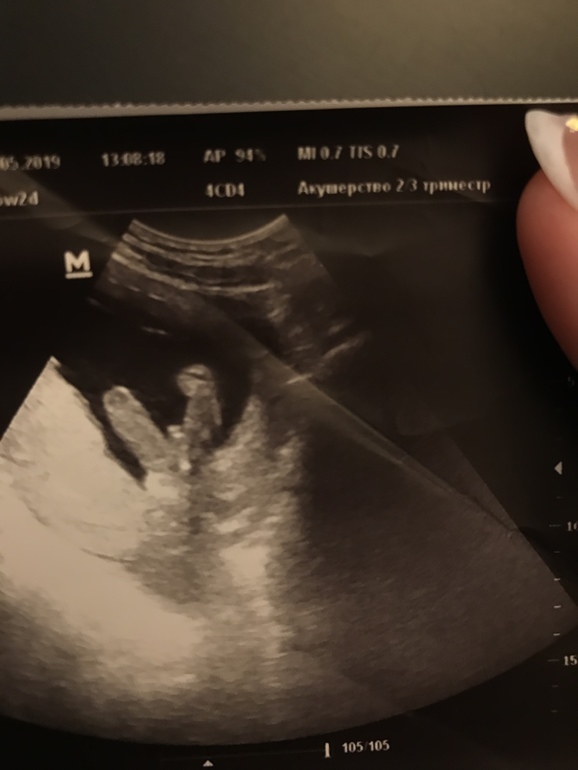

Ну точно же мальчик, да?😅

Пол малышаЯ тут немного паранойю в ожидании 4 недель до следующего скрининга...ну мальчишка же, точно, да?)

Вот вроде как помимо писюна и мошонку разглядеть можно, да и врач уверена на 100%... пока яички в 3Д не рассмотрю - не успокоюсь наверное )